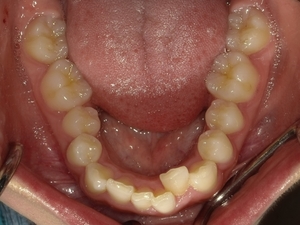

ガタガタとした歯並びや八重歯(叢生)CASE51